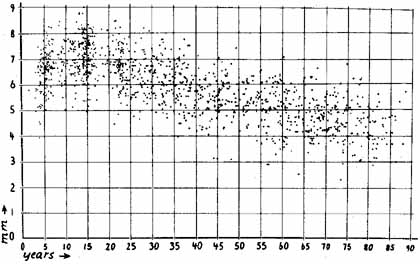

1. Loewenfeld IE: The Pupil: Anatomy, Physiology and Clinical Applications. Boston: Butterworth Heinemann, 1999 2. Wilhelm J, Wilhelm H, Moro S, Barbur JL: Pupil response components: Studies in patients with Parinaud's syndrome. Brain 125(10):2296, 2002 3. Bergamin O, Schoetzau A, Sugimoto K, Zulauf M: The influence of iris color on the pupillary light reflex. Graefes Arch Clin Exp Ophthalmol 236(8):567–570, 1998 4. Thompson HS, Franceschetti AT, Thompson PM: Hippus, semantic and historic considerations of the word. Am J Ophthalmol 71:1116, 1971 5. Loewenfeld IE: Pupillary changes related to age. In Thompson HS (ed): Topics in Neuro-ophthalmology. Baltimore: Williams & Wilkins, 1979:124–150 6. Bourne PR, Smith SA, Smith SE: Dynamics of the light reflex and the influence of age on the human pupil